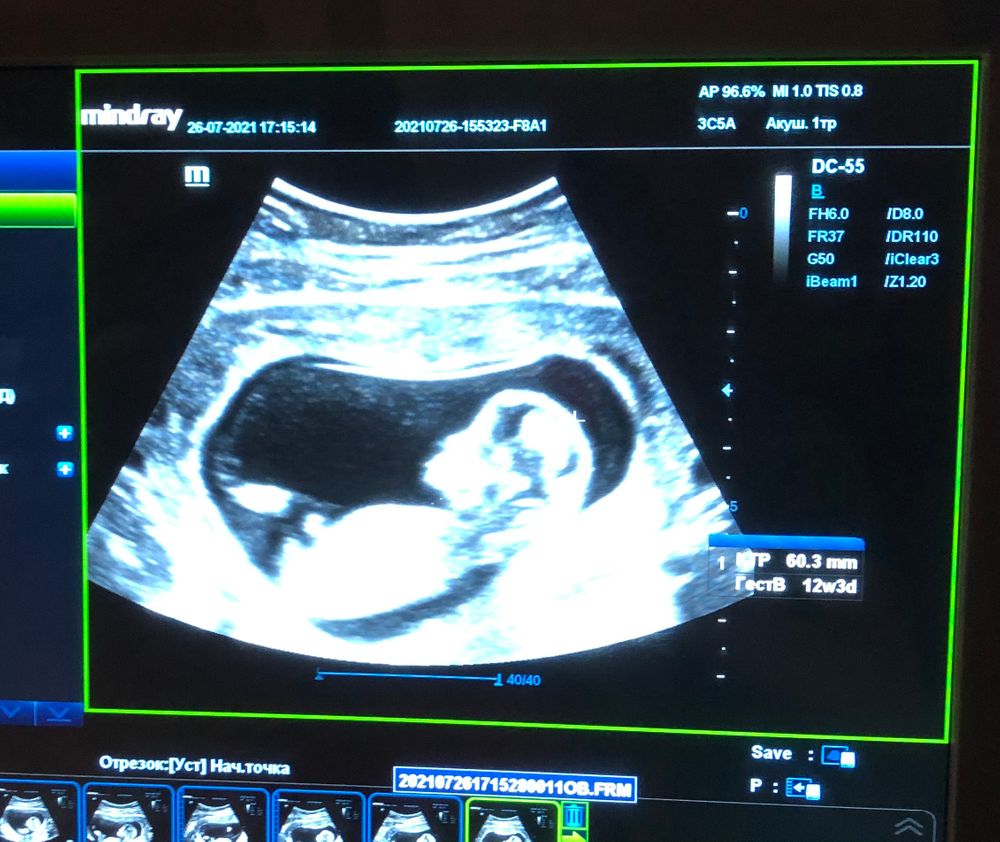

это 12 недель

А почему по половому бугорку не сработало? Бугорок девчачий в 12 недель